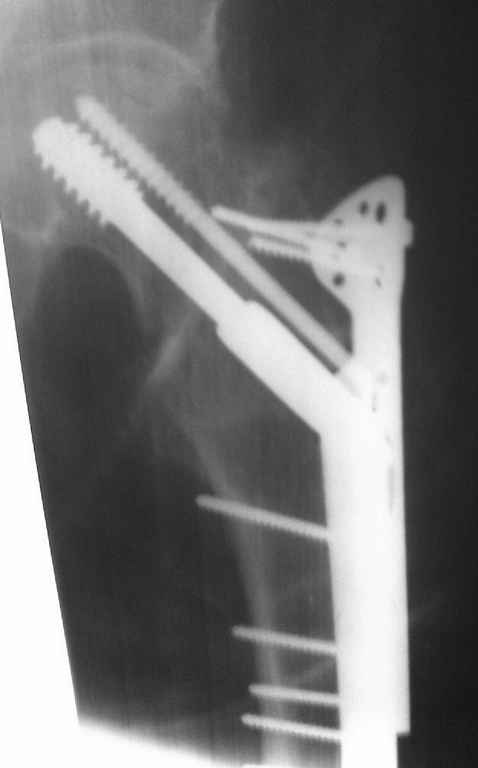

На снимках ложный сустав шейки бедра, несостоятельность фиксации. По положению шурупа можно предсказать ложный сустав, например, если screw backup за кортикальный слой около 15-20 мм, и также изменение угла от первоначального.

№4 результат на КТ